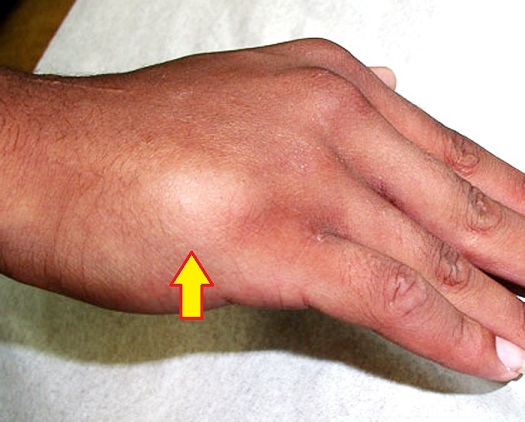

3-3: علائم وتشخیص شکستگی متاکارپ های کف دست: بدنبال شکستگی پشت دست متورم و دردناک شده و فشار به محل شکسته شده شدت درد را افزایش میدهد. پوست روی استخوان شکسته ممکن است کبود شود. مشت کردن دست معمولا شدت درد را افزایش میدهد. تشخیص این شکستگی ها با رادیوگرافی ساده است.